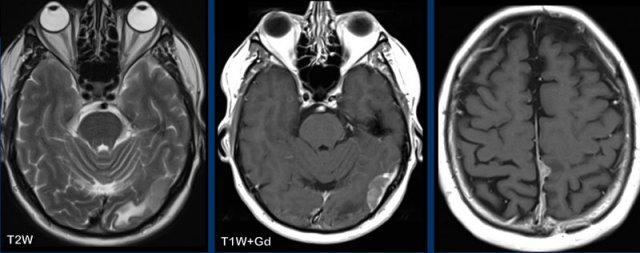

Các hình ảnh này của một phụ nữ 56 tuổi mắc ung thư vú.

Bệnh nhân có tổn thương xương sọ trên xạ hình xương chín năm trước, được cho là di căn xương.

Hiện tại bệnh nhân nhập viện với triệu chứng nôn và đau đầu.

Hình ảnh

Có một tổn thương ngoài trục lớn phù hợp với u màng não.

Có tăng sinh xương sọ rõ rệt và xâm lấn xoang tĩnh mạch dọc trên.

Đây không phải là di căn xương do các dấu hiệu này và thực tế là tổn thương đã hiện diện trong chín năm.

Các hình ảnh này của một nam giới 58 tuổi mắc ung thư phổi.

Có hai tổn thương bắt chước hình ảnh của u màng não.

Tiếp tục xem các hình ảnh theo dõi…

Trên hình ảnh theo dõi sau 2 tháng, tổn thương phát triển đáng kể.

Hiện tại bờ tổn thương không đều.

Đây hóa ra là di căn màng cứng.

Các hình ảnh này của một phụ nữ mắc ung thư cổ tử cung.

Có một khối di căn xương cực kỳ lớn với xâm lấn màng cứng và lan rộng ra ngoài hộp sọ.

Lưu ý một tổn thương di căn nhu mô ở hố sau (đầu mũi tên).